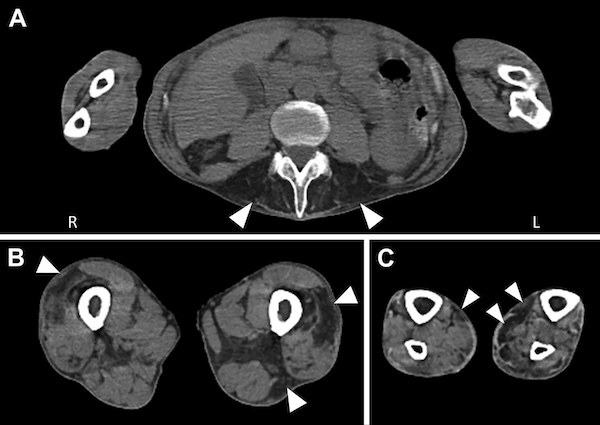

図. 骨格筋CT画像では、傍脊柱筋(A)、外側広筋、大内転筋、大腿二頭筋長頭(B)、腓腹筋内側頭(C)に脂肪変性を伴う筋萎縮を認める。